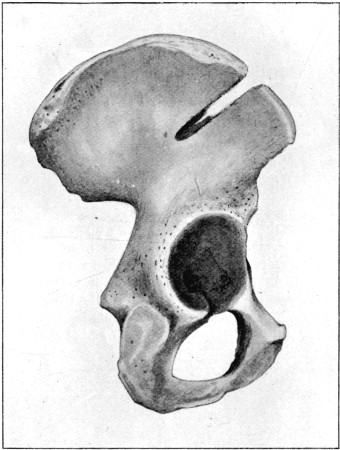

55. Gutter Fracture of Pelvis 191

55a. Diagram of 'Butterfly' Type 200